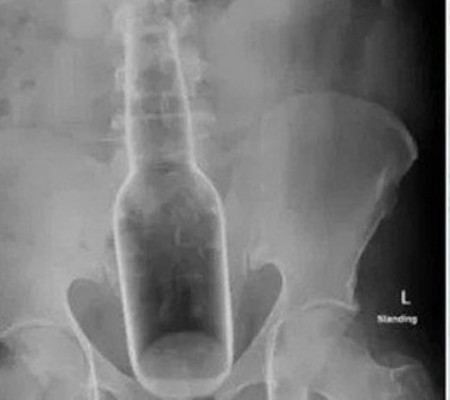

O hospital liberou imagens do caso como um alerta à população.

Um chinês de 60 anos sofreu um acidente com um vidro de perfume. Segundo ele, tudo aconteceu quando "tentava se coçar". O frasco acabou entrando pelo ânus do homem. As informações são do Extra.

Inicialmente, o homem foi a um pronto-socorro em Guangdong (Chona) reclamando de dores abdominais. Porém um exame de imagem revelou a presença do vidro de perfume, que media 18 centímetros de comprimento e 5 centímetros de largura, e originário da Flórida (EUA).

O paciente foi submetido a uma cirurgia, contou o "Metro". O hospital liberou imagens do caso como um alerta à população.

"O vidro inteiro estava no reto do paciente. Eu podia senti-la tocando o abdômen. Ele comentou que o seu ânus estava coçando", contou Lin Jun, médico que realizou o procedimento.